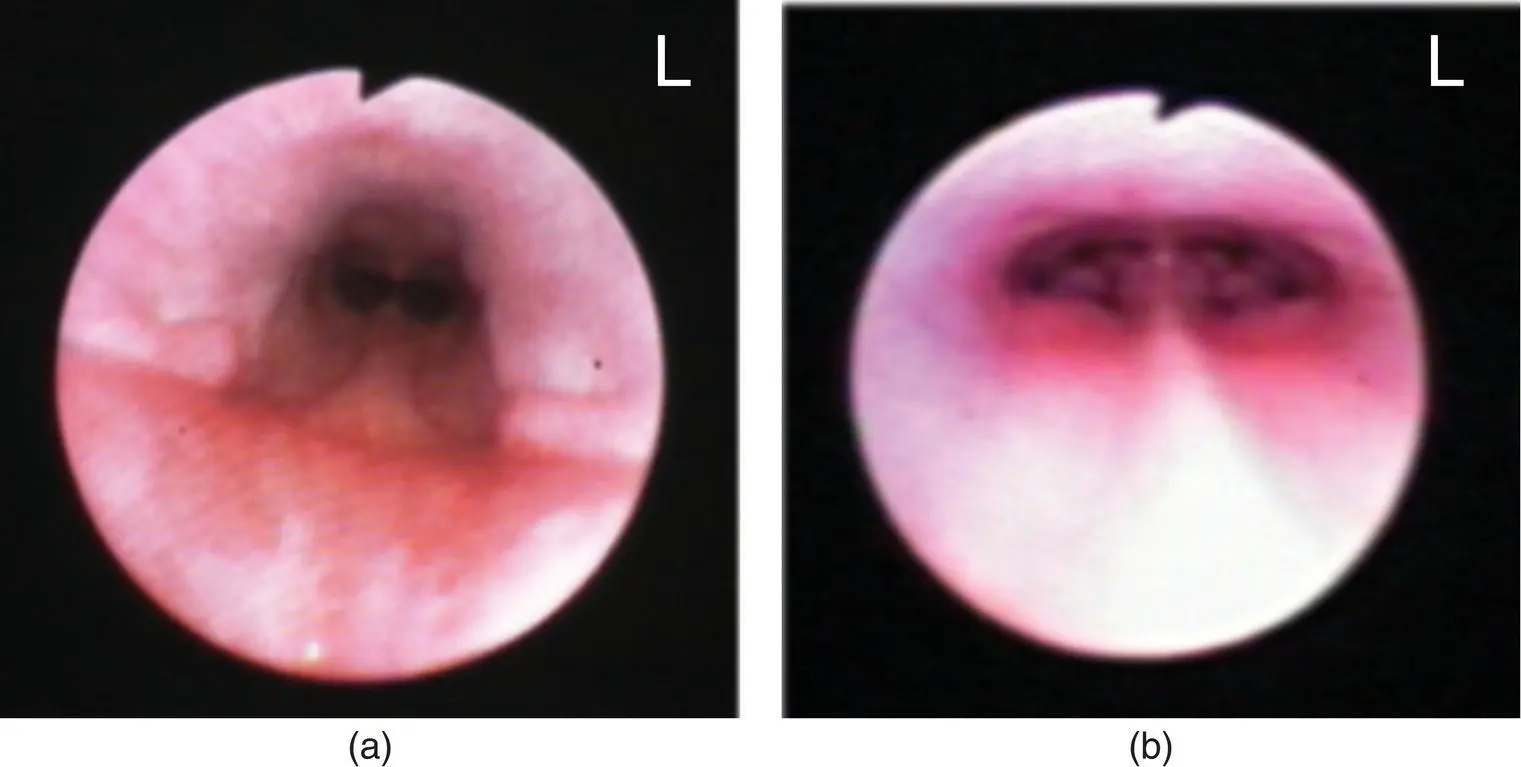

After the caudal nasopharynx is examined and samples are obtained for histopathology as indicated, a moistened surgical lap pad is used to pack the throat in order to prevent aspiration during rostral rhinoscopy. Equipment available for rostral rhinoscopy includes rigid endoscopes (with or without an external sheath), otoscopes, and small flexible endoscopes. Rigid scopes have better optics, are easier to maneuver, and come in smaller sizes, while flexible scopes allow greater access to the nasal cavity and can permit examination of the frontal sinuses when there is marked turbinate destruction (such as in nasal aspergillosis). Rigid scopes are available with viewing angles from 0 to 30°. Rhinoscopy can be performed using the telescope portion of the rigid scope alone (∼2.8 mm outer diameter) or by using the sheathed scope (∼5 mm outer diameter), which has flush and suction ports as well as a biopsy port available ( Figure 2.11). The biopsy port of the sheath will accept standard endoscopic biopsy or foreign body retrieval instruments.

Figure 2.11 The sheath (∼5 mm outer diameter) for the telescope portion of the rigid scope (∼2.8 mm outer diameter) has flush and suction ports (a) as well as a biopsy port (b) available.